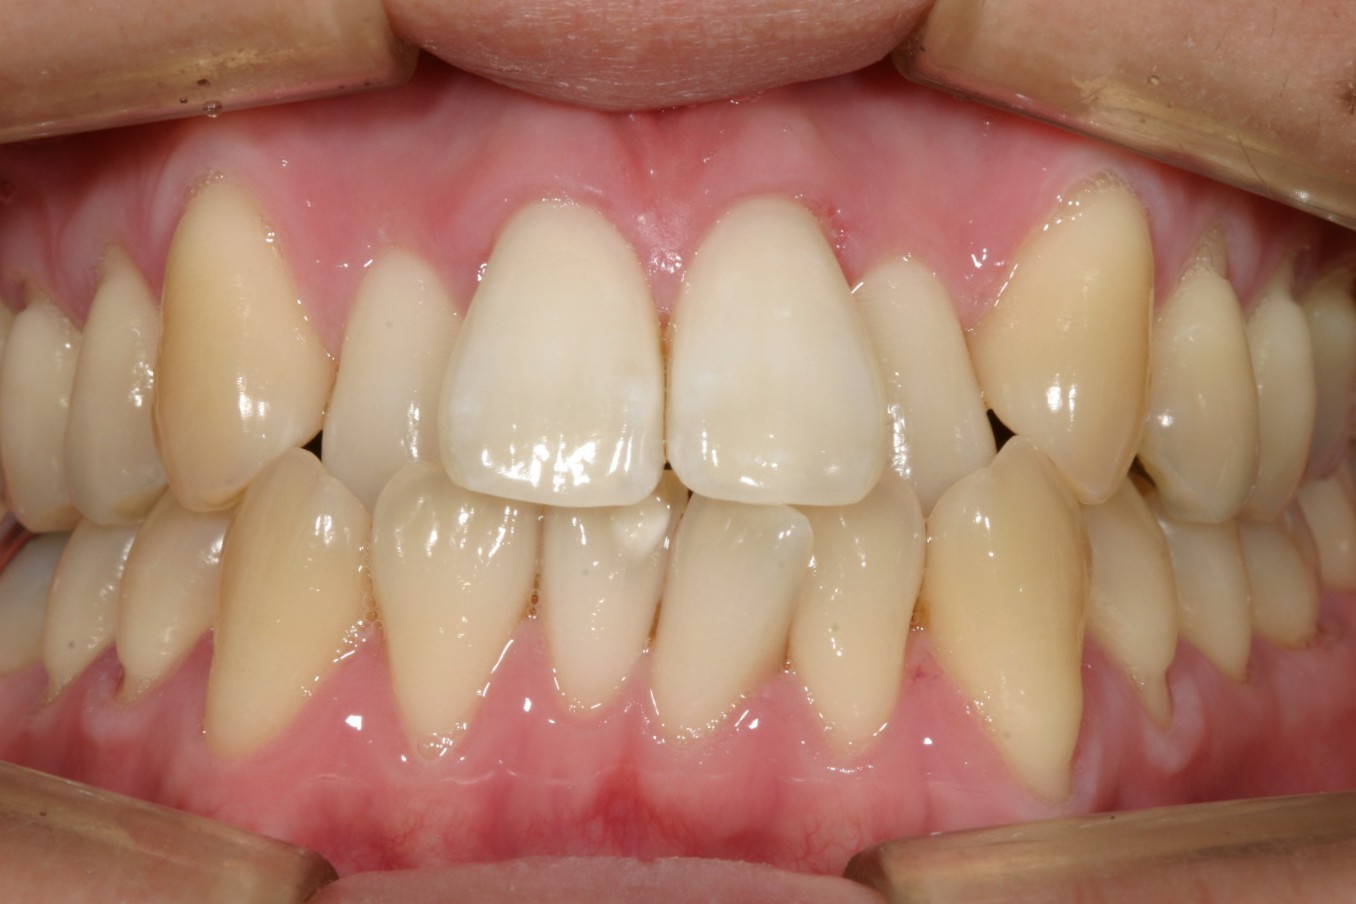

前歯が飛び出しガタガタしている。

前歯がすご出て又犬歯も飛び出しています。

下顎もアーチが狭い為にガタガタしています。

側面観も叢生が目立ちます。